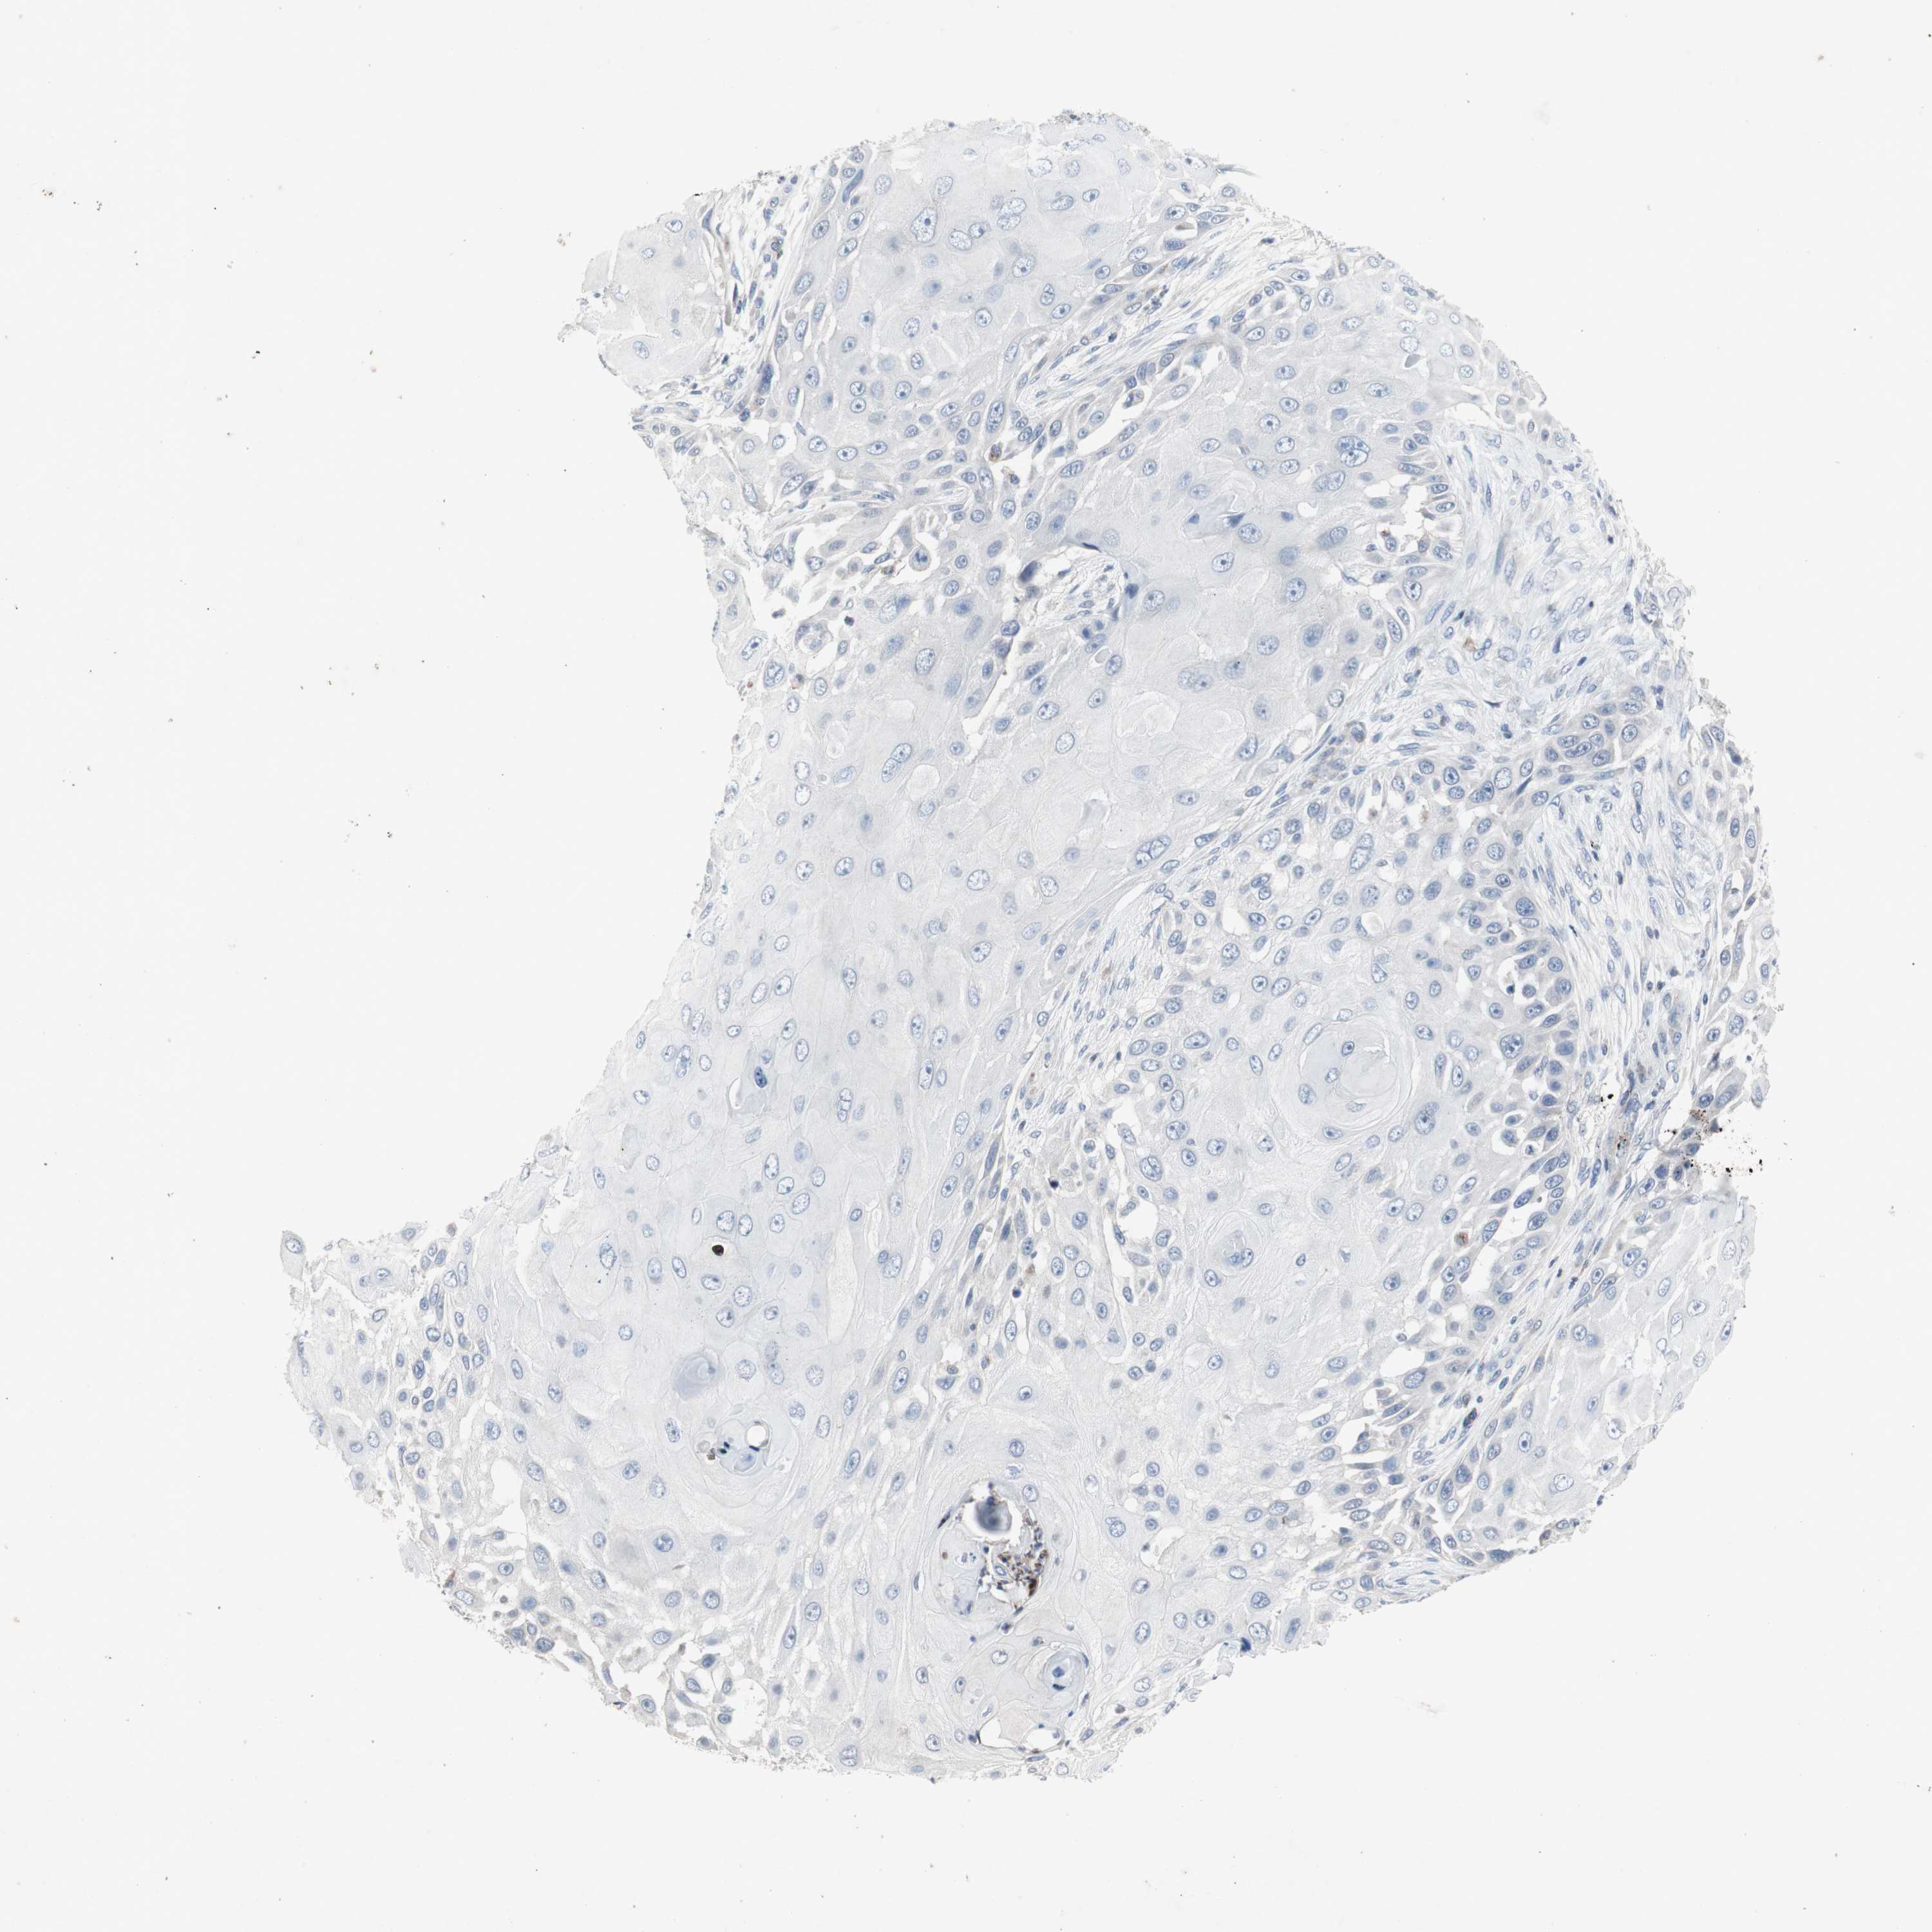

SKIN CANCER - Protein expressioni

A mouse-over function shows sample information and annotation data. Click on an image to view it in a full screen mode. Samples can be filtered based on level of antibody staining by selecting one or several of the following categories: high, medium, low and not detected. The assay and annotation is described here.

Antibody stainingi

Antibody staining in the annotated cell types in the current human tissue is reported as not detected, low, medium, or high, based on conventional immunohistochemistry profiling in selected tissues. This score is based on the combination of the staining intensity and fraction of stained cells.

Each image is clickable and will lead to virtual microscopy that enables deeper exploration of all samples and also displays staining intensity scores, fraction scores and subcellular localization as well as patient and tissue information for each sample.

Antibody HPA008732

Staining

High

Medium

Low

Not detected

Intensity

Strong

Moderate

Weak

Negative

Quantity

>75%

75%-25%

<25%

None

Location

Nuclear

Cytoplasmic/membranous

Cytoplasmic/membranous,nuclear

Squamous cell carcinoma, NOS

Basal cell carcinoma